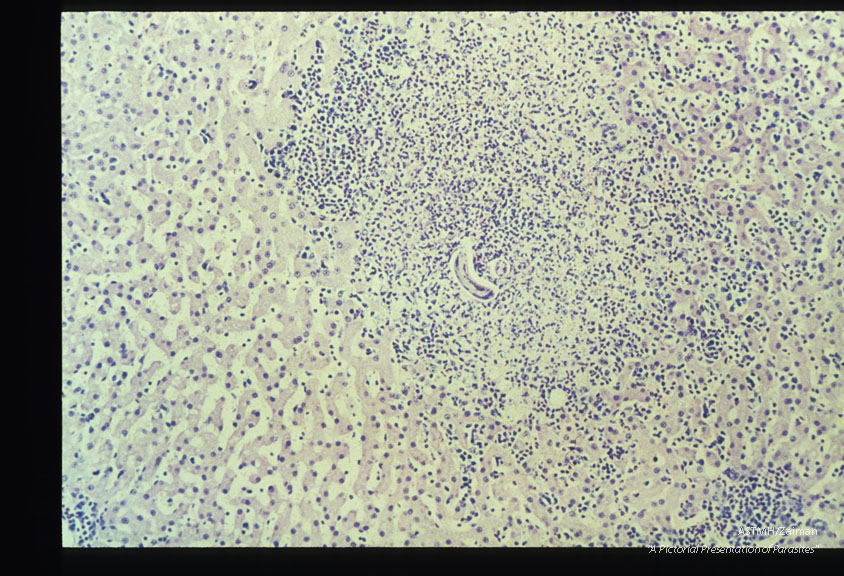

Typical hepatic granuloma containing a larva. Natural infection in a cat.

Toxocara canis

Description: Typical hepatic granuloma containing a larva. Natural infection in a cat.